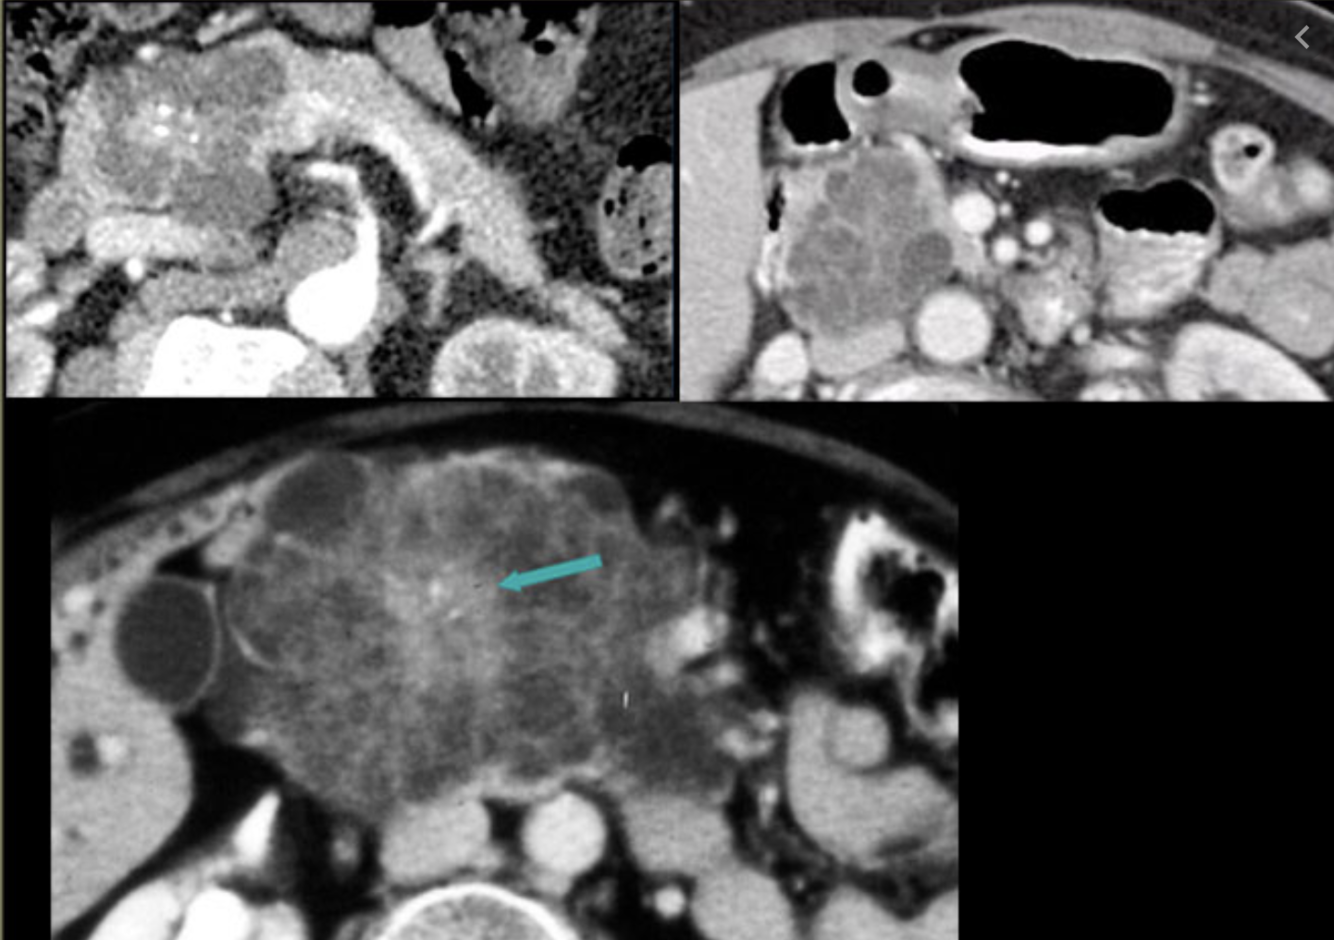

Name the most common met to the pancreas

RCC!